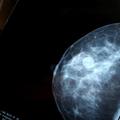

Malomarnost 'Pozabili' obvestiti bolnice z rakom V eni izmed britanskih bolnišnic so "pozabili" obvestiti ženske, pri katerih so odkrili raka na dojkah. Bolnišnica je ž…